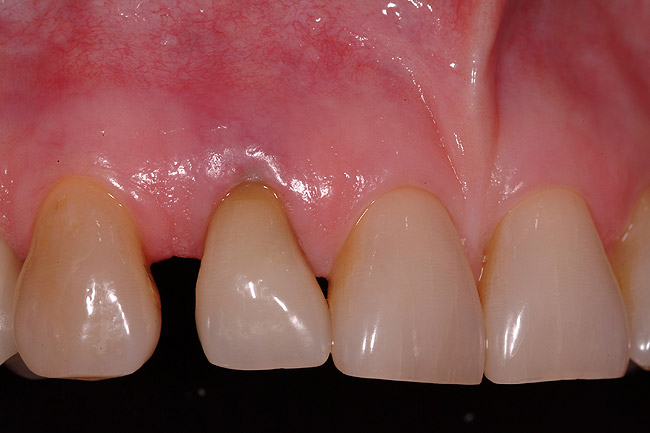

After the curing process, the complex was removed from the mouth, and inspection of the provisional complex showed the provisional coping registered in the tooth-shell composite complex (Figure 12). The margins were corrected with flowable composite, and the provisional was contoured. The final provisional can be seen in Figure 13. The provisional was filled with provisional cement (Figure 14) and placed over the abutment. After the cement set, and cement expressed into the sulcular space was removed, an explorer was used to remove the excess cement from the sulcular space. A peri-apical x-ray was taken to evaluate the peri-implant space.

The restoration was evaluated for occlusal contact. In any clinical case, if any occlusion exists on the implant restoration, it must be removed so that a non-functional restoration exists. This allows for the implant complex to mature free of occlusion for the 3-month healing phase. The immediate postoperative clinical view of this case, centric occlusion, can be seen in Figure 15, while the complete postoperative facial view is seen in Figure 16. Note how the contoured line angles and facial emergence profile of the retrofitted natural tooth allows for passive pressure on the natural tissue emergence profiles preserved throughout the surgical process. The immediate postoperative digital peri-apical radiograph can be seen in Figure 17. The implant was allowed to integrate for 3 months, at which time the soft tissue contours will have had the same time frame to mature. The provisional restoration will then be removed, and routine implant prosthetic procedures will be initiated.

Figure 15  Immediate postoperative clinical view.

Figure 15

Figure 16  Immediate postoperative facial view.

Figure 16